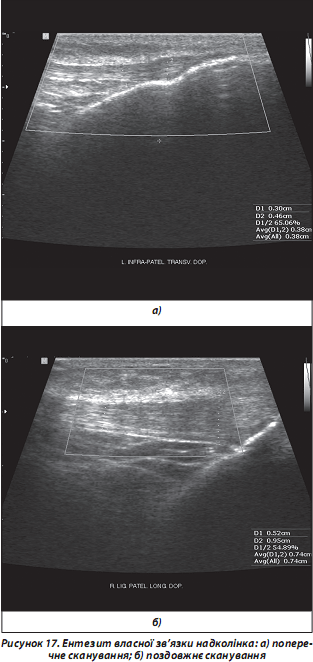

г) ентезити та ентезопатії. Досвід ревматологів-клініцистів свідчить, що упродовж тривалого часу ентезити (запалення ентезів — місць прикріплення до кістки зв’язок, сухожиль, апоневрозів, суглобових капсул) можуть бути єдиними клінічними ознаками РЗ у дебюті їх розвитку, а також передують розвитку синовітів суглобів нижніх кінцівок у хворих на РА та АС (рис. 17) [Коваленко В.Н., Борткевич О.П., 2004; Рекалов Д.Г., Борткевич О.П., 2011; McGonagle D. et al., 1998].